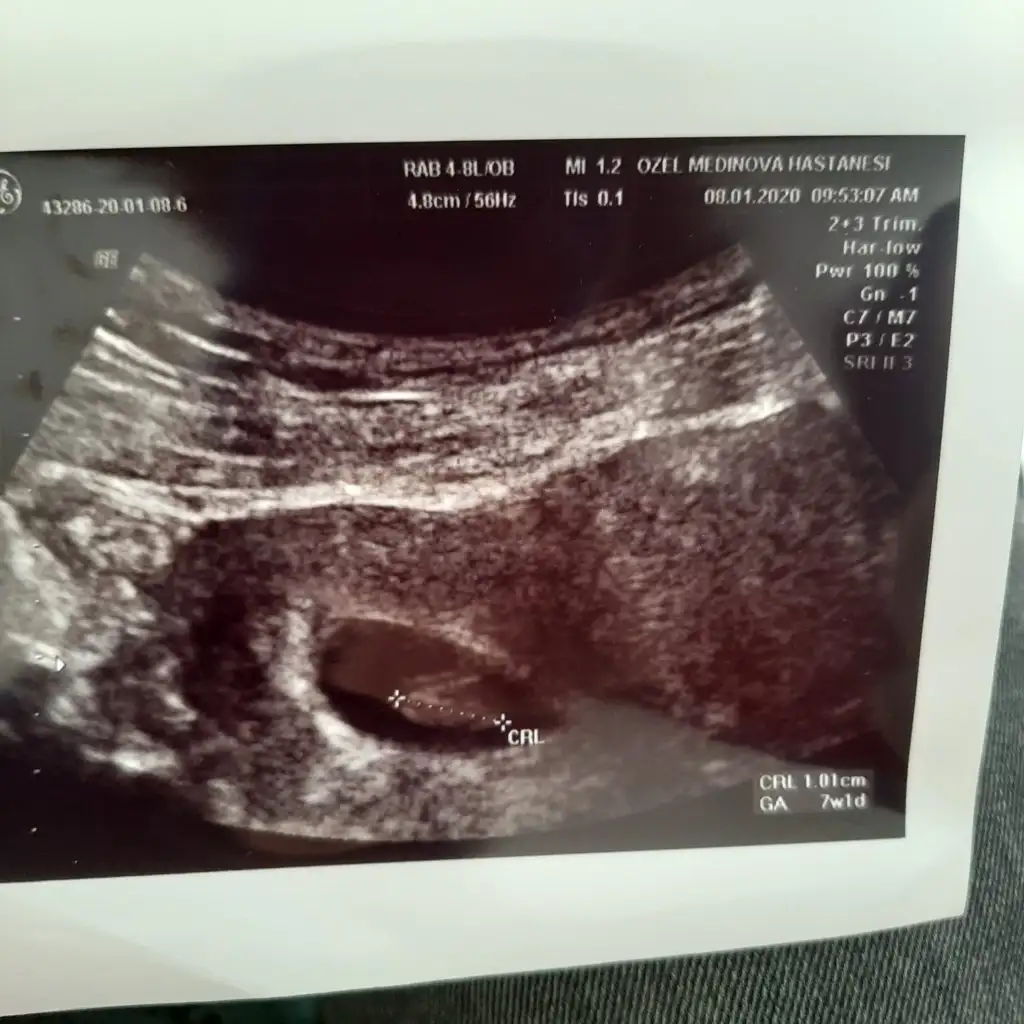

Benimkine de bakabilir misin

• 83B27EB4-A673-4EC3-A7D9-98DBA529FA95.webp

83B27EB4-A673-4EC3-A7D9-98DBA529FA95.webp

22,1 KB · Görüntüleme: 62